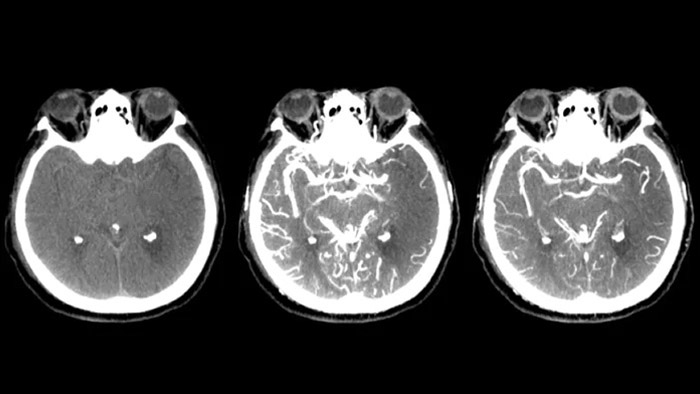

SmartCT Vaso IV

Comprobar la ubicación y la longitud del coágulo

SmartCT Vaso permite la visualización más allá del coágulo con imágenes periprocedimiento de las caras distales de los vasos en el accidente cerebrovascular isquémico. SmartCT Vaso es una técnica de adquisición basada en una TC de haz cónico y una inyección de contraste intrarterial. Permite la visualización más allá del coágulo con imágenes periprocedimiento de las caras distales de los vasos en el accidente cerebrovascular isquémico. Mediante el llenado retrógrado, se ven las estructuras de los vasos antes y después del coágulo. SmartCT Vaso 3D Roadmap puede utilizarse para visualizar los dispositivos de recuperación de coágulos.